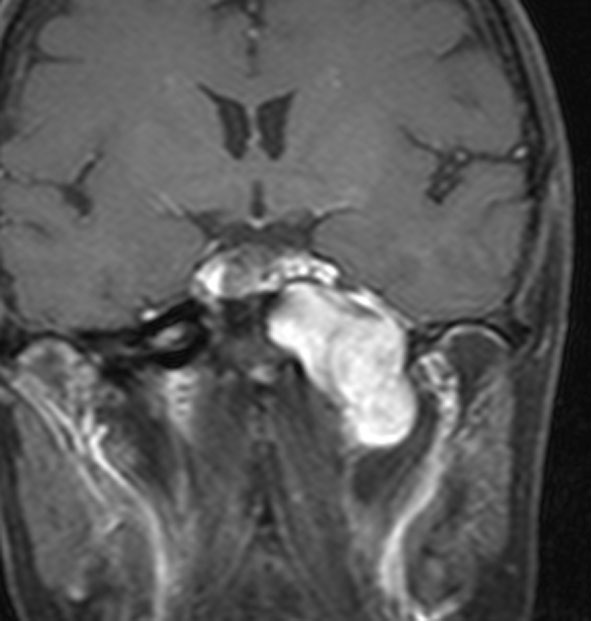

典型的な例2

40代で発症したものです。手術リスクが高いので定位分割放射線治療 fSRT をしました。50グレイを25分割,1回線量2グレイです。以来,18年間が経過しますが腫瘍は2/3くらいに縮小して,そのままです。新たな症状もありません。この腫瘍への手術侵襲は大きいので定位放射線治療は有力な治療選択肢です。